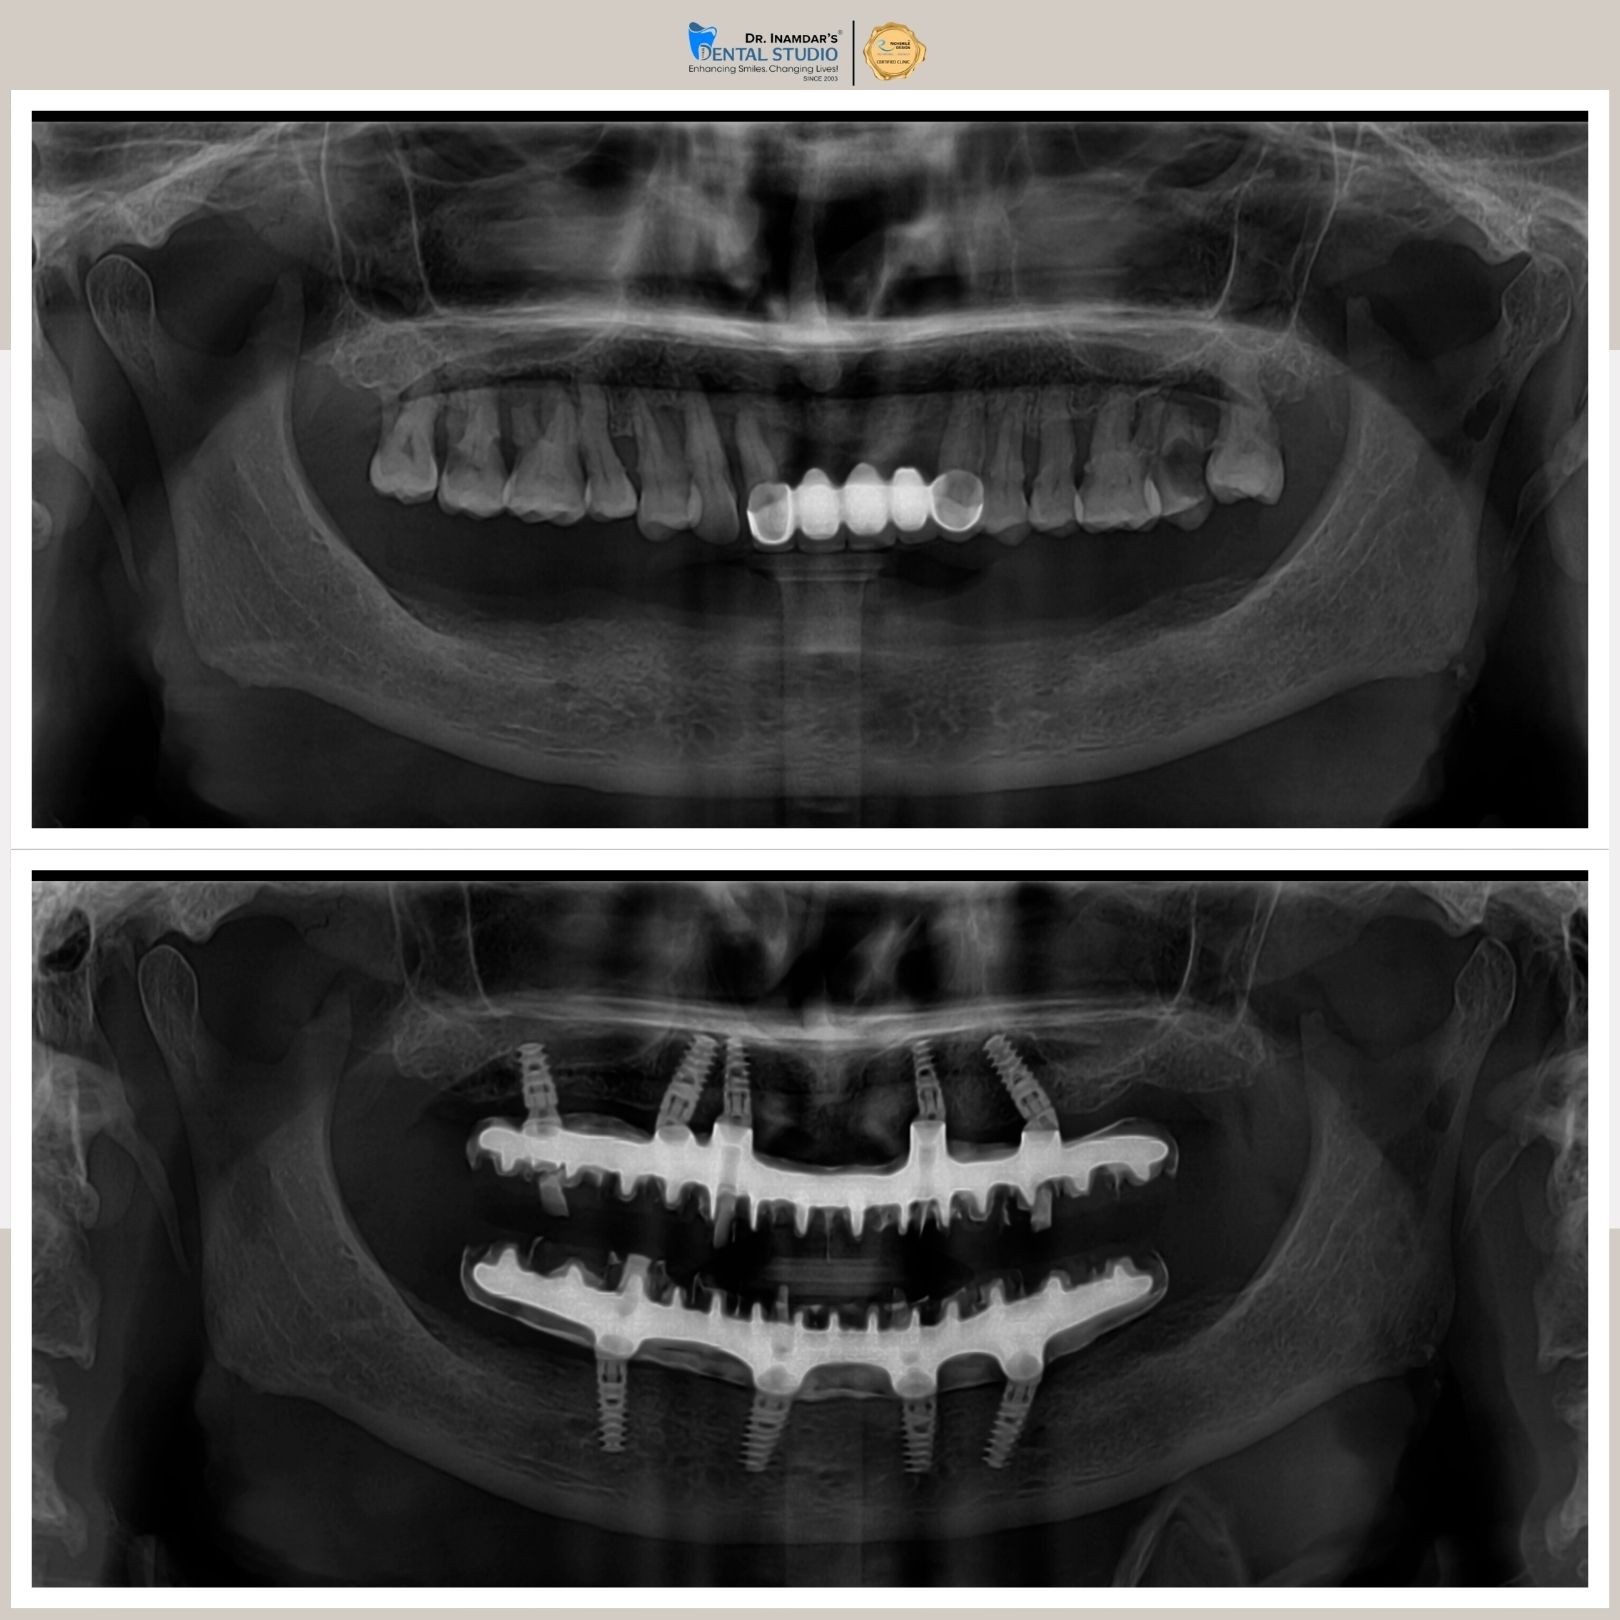

Full mouth dental implants are used to replace all missing teeth in the upper or lower jaw. A series of titanium implants are placed securely in the jawbone, and custom-made ceramic or zirconia crowns, are attached, restoring a full set of functional, natural-looking teeth.

The dental implant procedure typically involves placing the implant into the jawbone, followed by a healing period before attaching the crown.